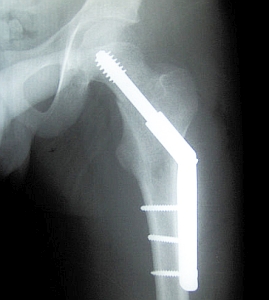

Hüftimplantat im Röntgen: Metall ist schlechtestes Material. Bild: Wikimedia